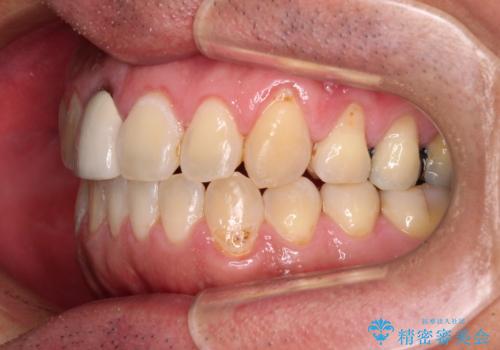

- 前歯のデコボコと上下のクロスバイトを気にして来院された患者様です。

インビザラインを用い、IPR(歯と歯の間を削る)と歯列全体を拡大させることで、歯並びを整えていくこととしました。

上の前歯が下の前歯を乗り越える際、奥歯がほとんど咬めない時期があり、乗り越えた後も、インビザライン特有の奥歯の咬みにくさが続きました。

咬み合わせ改善のために治療期間を要しましたが、最終的に奥歯はしっかりと咬めるようになりました